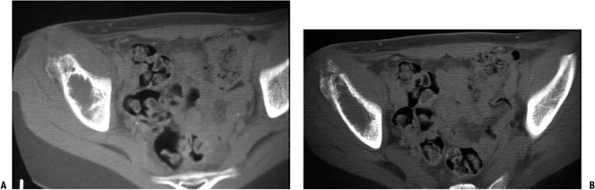

Figure 6.2-4 Computed tomographic scans demonstrating the lytic destructive changes of the ilium.